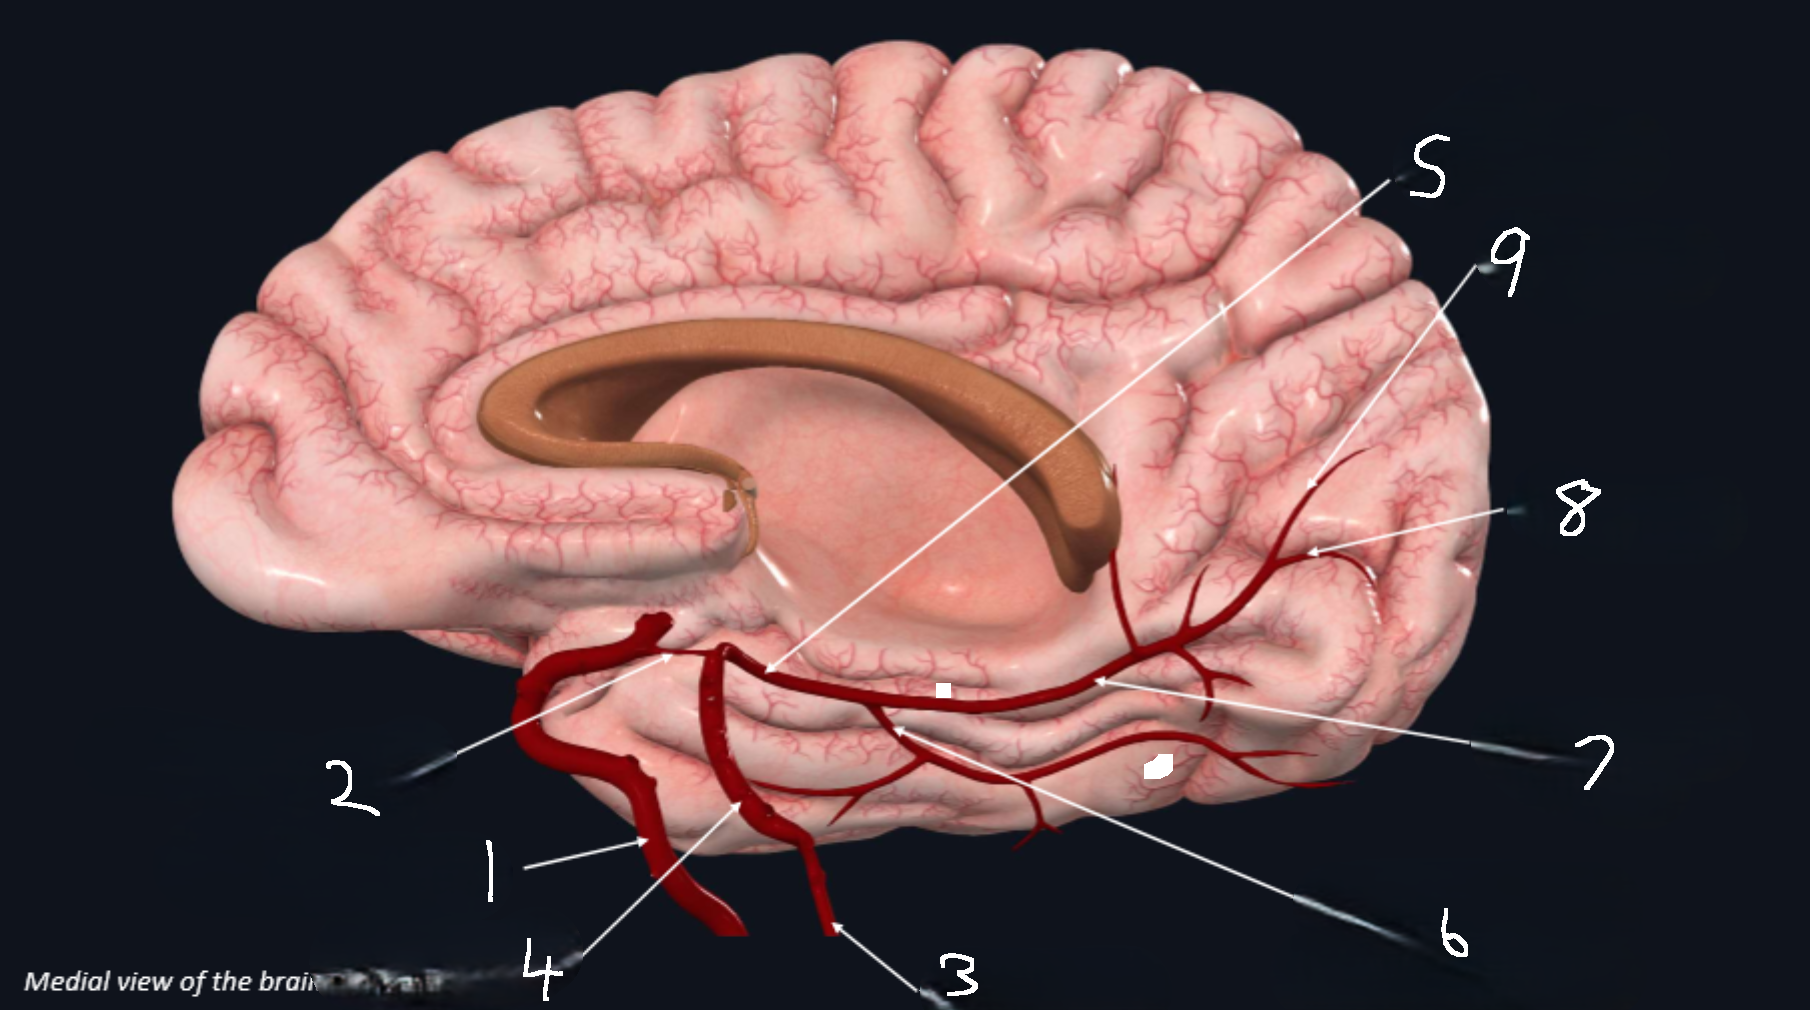

What is 1?

internal carotid artery

What is 2?

posterior communicating artery

What is 3?

vertebral artery

What is 4?

basilar artery

What is 5?

posterior cerebral artery

What is 6?

lateral occipital artery

What is 7?

medial occipital

What is 8?

calcarine branch

What is 9?

parieto-occipital branch